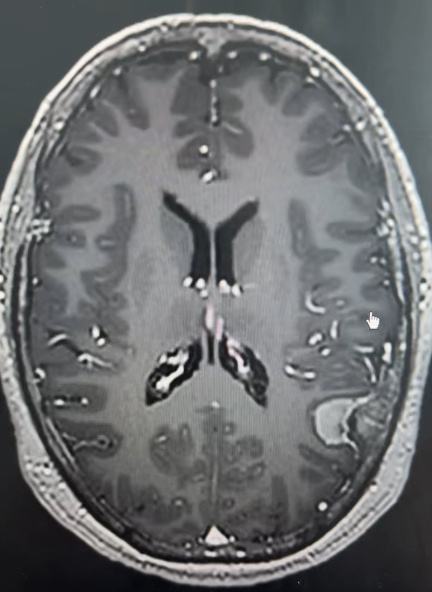

在河北省人民医院,一位63岁女性患者正面临 “生死时速” 的考验。患者因 “右上肢肌力下降伴部分失语5天,加重1天” 入院,病情进展较快——入院仅1天便完全失语,偏瘫症状进一步加重。两院专家联合评估,制定个性化手术方案。

术中利用导航、超吸、电生理等辅助手段,王虎主任成功将肿瘤全部切除,术后患者症状得到明显改善。